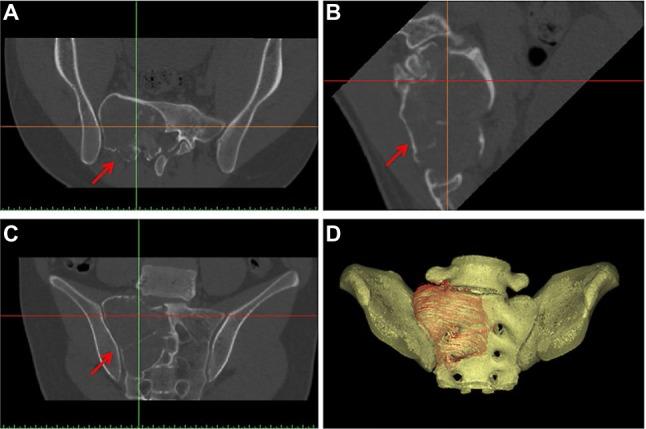

With advances in both medical imaging and computer programming, two-dimensional axial images can be processed into other reformatted views (sagittal and coronal) and three-dimensional (3D) virtual models that represent a patients' own anatomy. This processed digital information can be analyzed in detail by orthopedic surgeons to perform patient-specific orthopedic procedures. The use of 3D printing is rising and has become more prevalent in medical applications over the last decade as surgeons and researchers are increasingly utilizing the technology's flexibility in manufacturing objects. 3D printing is a type of manufacturing process in which materials such as plastic or metal are deposited in layers to create a 3D object from a digital model. This additive manufacturing method has the advantage of fabricating objects with complex freeform geometry, which is impossible using traditional subtractive manufacturing methods. Specifically in surgical applications, the 3D printing techniques can not only generate models that give a better understanding of the complex anatomy and pathology of the patients and aid in education and surgical training, but can also produce patient-specific surgical guides or even custom implants that are tailor-made to the surgical requirements. As the clinical workflow of the 3D printing technology continues to evolve, orthopedic surgeons should embrace the latest knowledge of the technology and incorporate it into their clinical practice for patient-specific orthopedic applications. This paper is written to help orthopedic surgeons stay up-to-date on the emerging 3D technology, starting from the acquisition of clinical imaging to 3D printing for patient-specific applications in orthopedics. It 1) presents the necessary steps to prepare the medical images that are required for 3D printing, 2) reviews the current applications of 3D printing in patient-specific orthopedic procedures, 3) discusses the potential advantages and limitations of 3D-printed custom orthopedic implants, and 4) suggests the directions for future development. The 3D printing technology has been reported to be beneficial in patient-specific orthopedics, such as in the creation of anatomic models for surgical planning, education and surgical training, patient-specific instruments, and 3D-printed custom implants. Besides being anatomically conformed to a patient's surgical requirement, 3D-printed implants can be fabricated with scaffold lattices that may facilitate osteointegration and reduce implant stiffness. However, limitations including high cost of the implants, the lead time in manufacturing, and lack of intraoperative flexibility need to be addressed. New biomimetic materials have been investigated for use in 3D printing. To increase utilization of 3D printing technology in orthopedics, an all-in-one computer platform should be developed for easy planning and seamless communications among different care providers. Further studies are needed to investigate the real clinical efficacy of 3D printings in orthopedic applications.

随着医学成像和计算机编程技术的进步,二维轴向图像可以被处理成其他重新格式化的视图(矢状面和冠状面)以及代表患者自身解剖结构的三维(3D)虚拟模型。骨科医生可以详细分析这些处理后的数字信息,以实施针对患者的骨科手术。在过去十年中,3D打印的应用不断增加,在医疗领域也变得更加普遍,因为外科医生和研究人员越来越多地利用该技术在制造物体方面的灵活性。3D打印是一种制造工艺,其中塑料或金属等材料以层状沉积,从数字模型创建3D物体。这种增材制造方法的优点是能够制造具有复杂自由形状几何结构的物体,这是传统减材制造方法无法实现的。特别是在外科应用中,3D打印技术不仅可以生成能更好地理解患者复杂解剖结构和病理情况的模型,并有助于教育和外科培训,还可以生产针对患者的手术导板,甚至定制植入物,以满足手术要求。随着3D打印技术临床工作流程的不断发展,骨科医生应掌握该技术的最新知识,并将其纳入针对患者的骨科临床实践中。本文旨在帮助骨科医生了解新兴的3D技术的最新情况,从获取临床影像到用于骨科患者特定应用的3D打印。它1)介绍了准备3D打印所需医学图像的必要步骤,2)回顾了3D打印在针对患者的骨科手术中的当前应用,3)讨论了3D打印定制骨科植入物的潜在优势和局限性,4)提出了未来发展方向。据报道,3D打印技术在针对患者的骨科领域有益,例如用于创建手术规划、教育和外科培训的解剖模型、针对患者的器械以及3D打印定制植入物。除了在解剖学上符合患者的手术要求外,3D打印植入物还可以制造带有支架晶格结构,这可能有助于骨整合并降低植入物的硬度。然而,包括植入物成本高、制造周期长以及术中缺乏灵活性等局限性需要得到解决。已经对用于3D打印的新型仿生材料进行了研究。为了提高3D打印技术在骨科中的利用率,应开发一个一体化计算机平台,以便在不同医疗服务提供者之间进行轻松规划和无缝沟通。需要进一步研究来调查3D打印在骨科应用中的实际临床疗效。